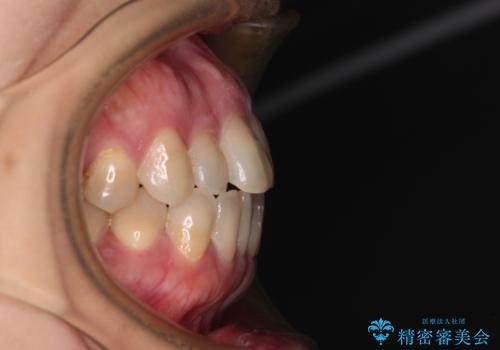

- 前歯のデコボコと口元の突出感を気にして来院された患者様です。

上下前歯がくちばしのように突出していたため、上下左右の第一小臼歯4本を抜歯し、ワイヤー装置にて矯正治療を行うこととしました。

上顎骨に対して下顎骨がやや前方位に位置しているため、歯肉退縮を回避するために下顎前歯をあまり内側に移動させることができない状況でしたが、十分に口元の突出感を改善することができました。